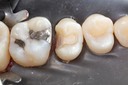

Mark Chun #17 pre-op